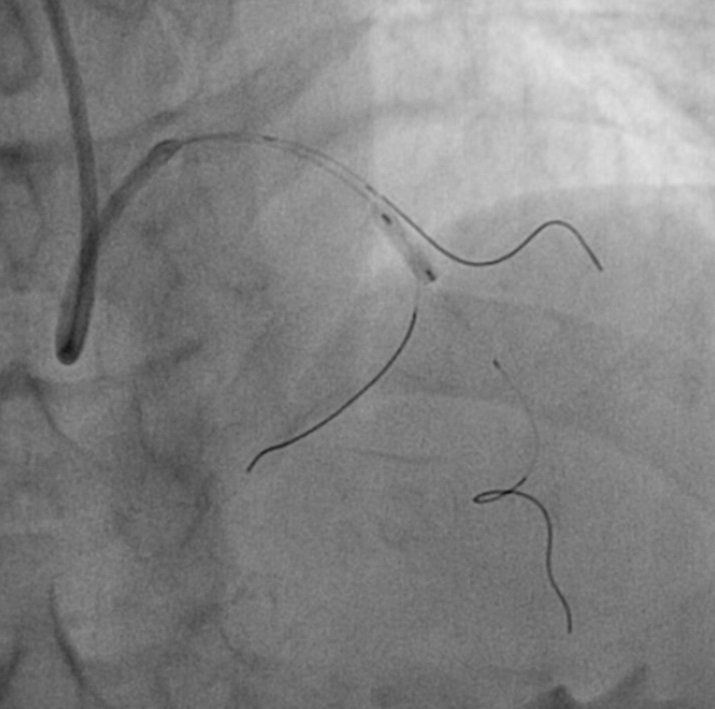

Negli anni di formazione, ha dedicato gran parte del tempo libero per “imparare il mestiere, andando a bottega” presso altri centri (soprattutto l’ospedale di Bergamo); è quindi stato protagonista nell’introdurre all’ospedale di Lecco le attività di angioplastica coronarica (trattamenti tran-scatetere per curare angina e infarto, determinati da occlusioni delle arterie del cuore, le coronarie).

Dal 2010 al pensionamento è stato responsabile dell’unità di Emodinamica dell’Ospedale di Lecco, ove nel corso degli anni, oltre all’angioplastica coronarica, sono stati intrapresi anche più complessi trattamenti trans-catetere di cardiopatie strutturali: sostituzione aortica trans-catetere (TAVI), trattamento trans-catetere della mitrale ed interventi di chiusura di pervietà del forame ovale (PFO), difetti interatriali (DIA), difetti interventricolari (DIV) e dell’auricola sinistra ecc.